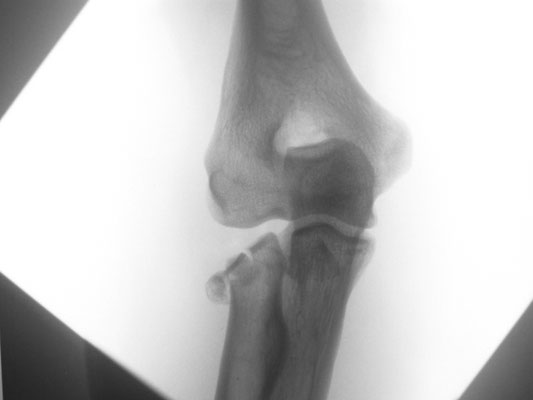

Ellenbogennaher Ellenbruch (Olecranonfraktur)

Der Ellenhaken (Olecranon) stellt den knöchernen Teil dar, über den die Kraft des Trizepsmuskels in den Unterarm geleitet wird und somit die aktive Streckung des Ellenbogens gegen Widerstand ermöglicht wird. Durch den Zug der Trizepssehne wird das kleine Knochenfragment weggezogen. Die Kraftübertragung des Muskels auf den Unterarm ist abgehängt. Insofern ergibt sich die Erfordernis, das Knochenteil und damit auch die Sehne des Trizeps wieder am Unterarm zu befestigen. Zusätzlich muss auch die Kongruenz des Gelenkes wieder hergestellt werden. Je nach dem, ob es sich um einen einfachen oder komplizierten Knochenbruch handelt, wird eine sog. Zuggurtungsosteosynthese mit zwei Drähten und einer Achterschlinge (Abb. 6a-b) oder eine Stabilisierung mit einer Platte durchgeführt.